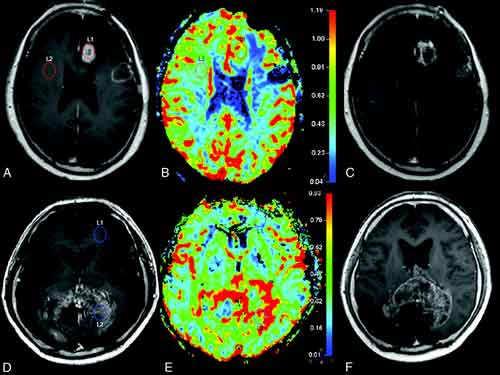

Images of Mgmt Glioblastoma

Mgmt Glioblastoma Photos

Mgmt Glioblastoma Pictures

Mgmt Glioblastoma Images